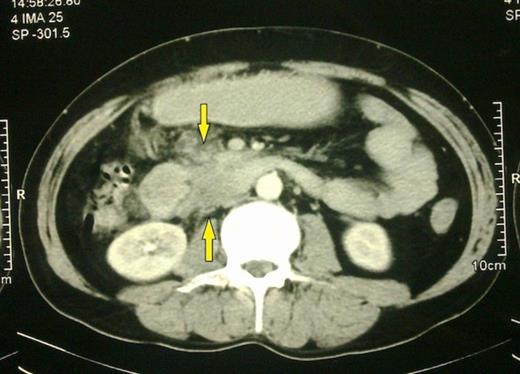

A 42 year old male presented in with pain in epigastrium since 25 days. Pain was mild in intensity, gradual in onset, continuous in nature and was aggravated on taking food and relieved on lying down. There was history of sensation of fullness after meals followed by vomiting of ingested food particles since 20 days. There was no history of fever, anorexia and weight loss, burning pain in upper abdomen, bleeding per rectum, jaundice or any urinary complaints. There was no past history of chronic cough with haemoptysis. There was no family history of tuberculosis. General physical examination was within normal limits. The USS of the abdomen was normal. However the CT showed an ill-defined soft tissue density thickening involving 3rd part of duodenum with surrounding soft tissue stranding extending to mesenteric fat with mild dilatation of proximal duodenum and stomach along with enlarged precaval nodes (Fig. 1). Upper GI endoscopy revealed a fold thickening at D3 with narrowing, scope was not negotiable beyond that part, biopsy was taken which showed lymphoplasmacytic infiltrate in lamina propria. There was no evidence of granuloma or parasite or dysplasia or malignancy (Fig. 2).